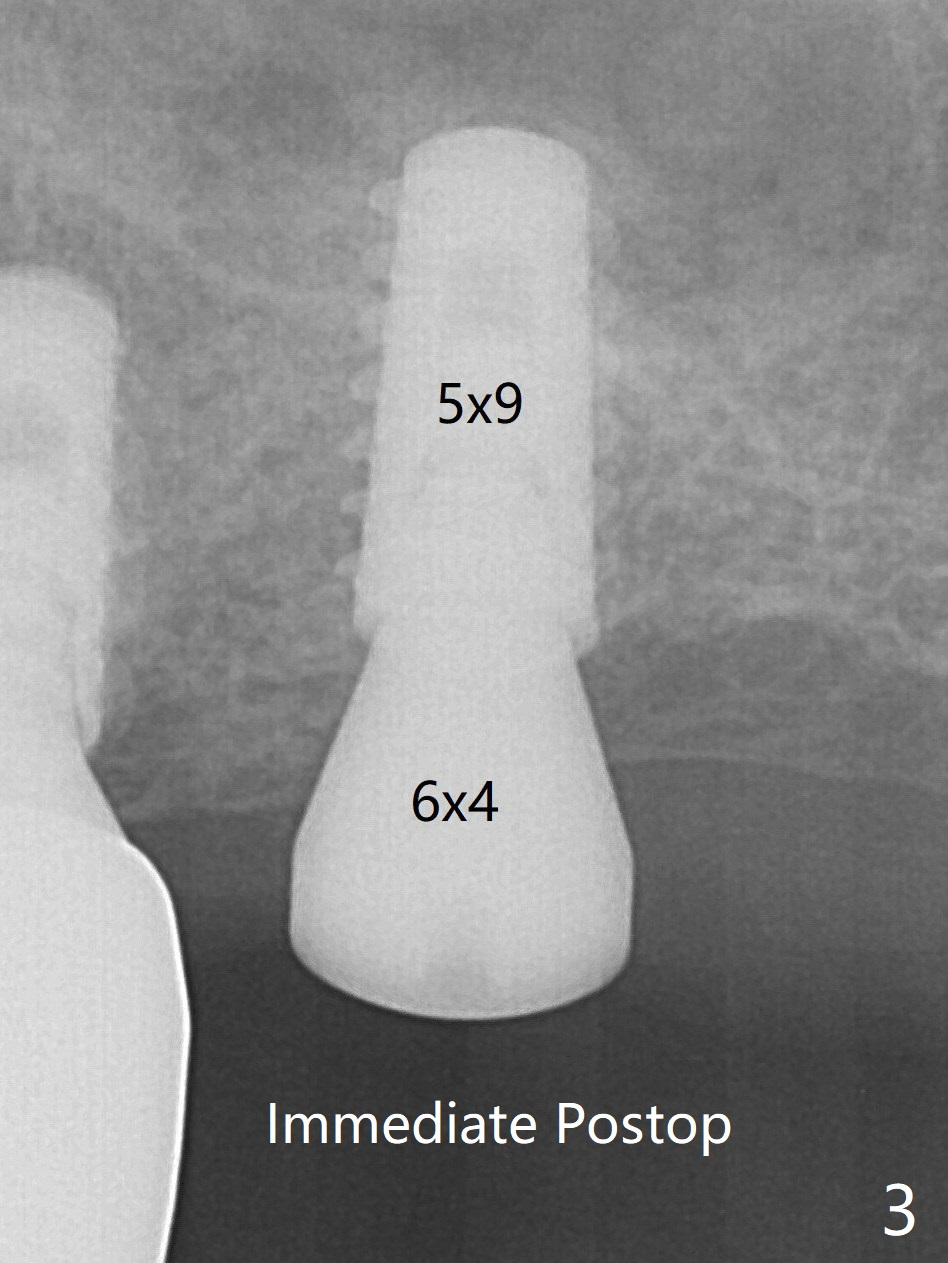

With more allograft for sinus lift, a 5x9 mm implant is inserted with >35 Ncm (Fig.3). The implant appears osteointegrated with sinus lift 2.5 months postop (Fig.5 *). Half month later, a pair abutment (5.5x4(4) mm; 25 Ncm) is placed at #15. When the patient returns 7 months postop, BWs are taken to confirm that the abutment at #15 is fully seated, whereas that at #14 is not (Fig.6 (>: gap)).